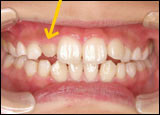

2番目の永久歯の生えるスペースが不足

【装置を入れて治療中】

装置で顎の幅を拡大して、スペースが確保されたことにより、2番目の永久歯が生えてきました

■正面から見た場合

【治療後】スペースがなく、うまく揃わなかった永久歯が、正常な状態に並びました

治療前

正面から見た場合	治療前

治療後

正面から見た場合	治療後